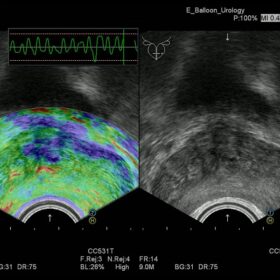

- Hitachi Real-time Tissue Elastography (HI-RTE)

Hitachi EUP-CC531 Endocavity Bi-Plane

Hitachi EUP-CC531S Endocavity Bi-Plane

Hitachi EUP-U533 Endocavity Bi-Plane